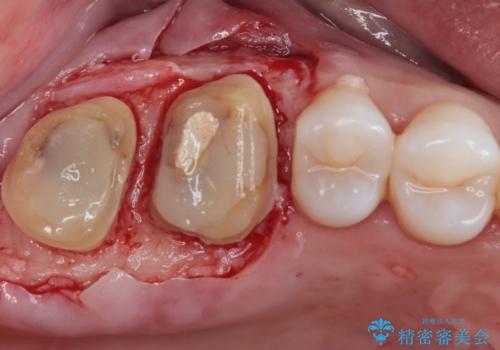

隣接する部分の間のむし歯が歯肉の奥深くにまで及んでおり、歯肉が腫れやすい状態となっていたため、歯肉の切除並びに歯槽骨の形態修正を行い、虫歯が歯肉の外に出てくるようにした上で、オールセラミックにて補綴することとしました。

歯間ブラシを通す度に出血をするのは、ご自身の磨き方が悪いからと思っていらっしゃいましたが、治療後は全く出血することがなくなり、患者様には大変満足していただきました。